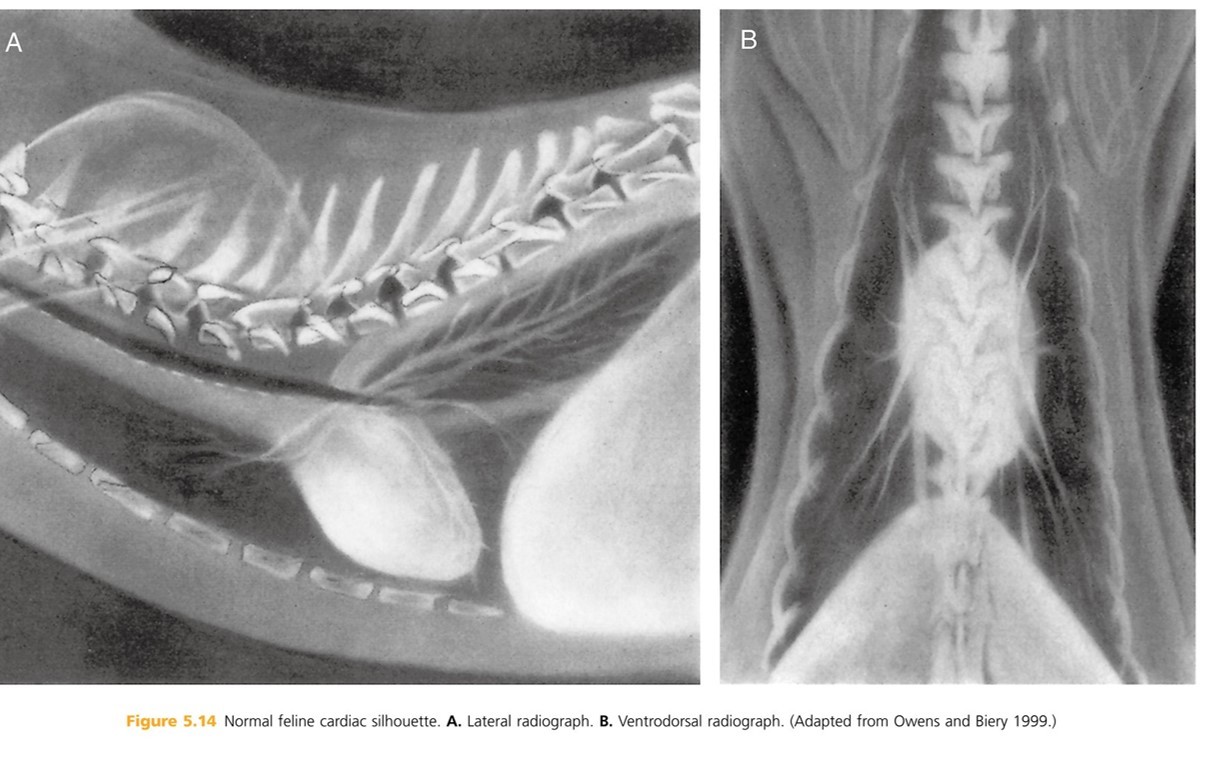

Older cats loose the elasticity of the aortic wall resulting in an altered appearance to cardiovascular structures. The heart moves more ____ to the sternum and the aortic arch b/c more prominent (described as “____” or “_____”) and may be mistaken for a cranial mediastinal or pulmonary mass on (_____ radiographs). On _____ radiographs, the desecending aorta appears more tortuous, wavy , or redundant

parallel

Kinked or knuckled

VD/DV- (B)

lateral - (A) BTW, hypertension can also result in a more tortuous descending aorta